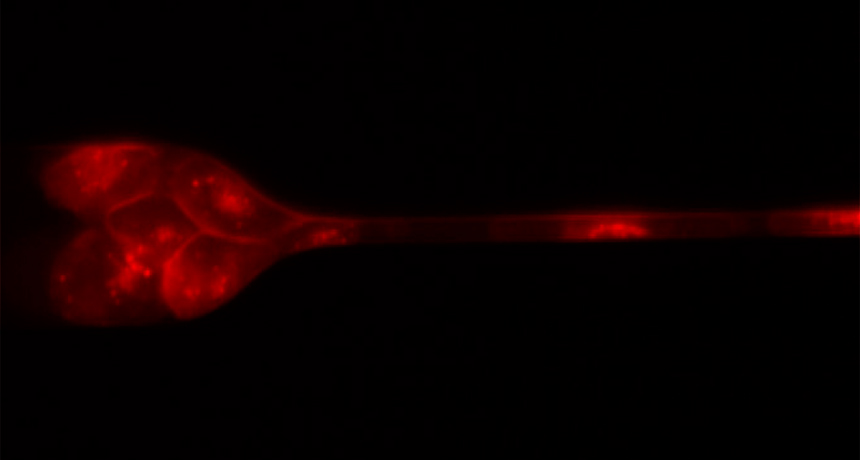

SQUEEZE PLAY  As a clump of stained human breast cancer cells approaches a capillary tube, the cells adjust their formation and their shape to pass through the narrow space.

S.H. Auet al/PNAS 2016